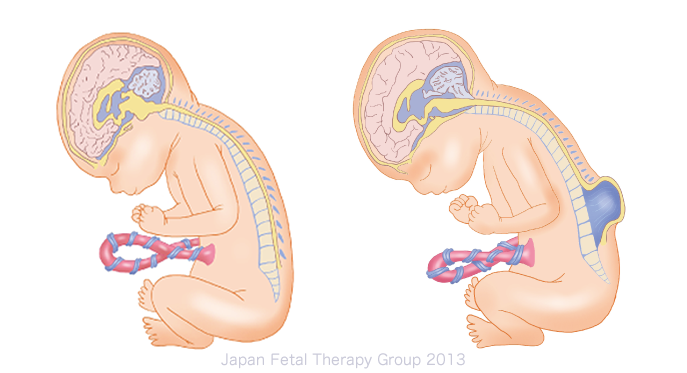

Аномалия Арнольда-Киари: MRI снимки